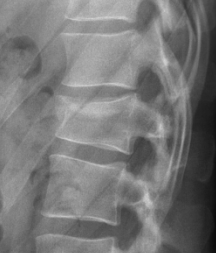

12

Q

Lesão degenerativa discal

aonde estão as lesões nas imagens?

A

1. Lesão degenerativa discal de C5-C6- C7

2. Lesão degenerativa discal de L2-L3-L4-L5